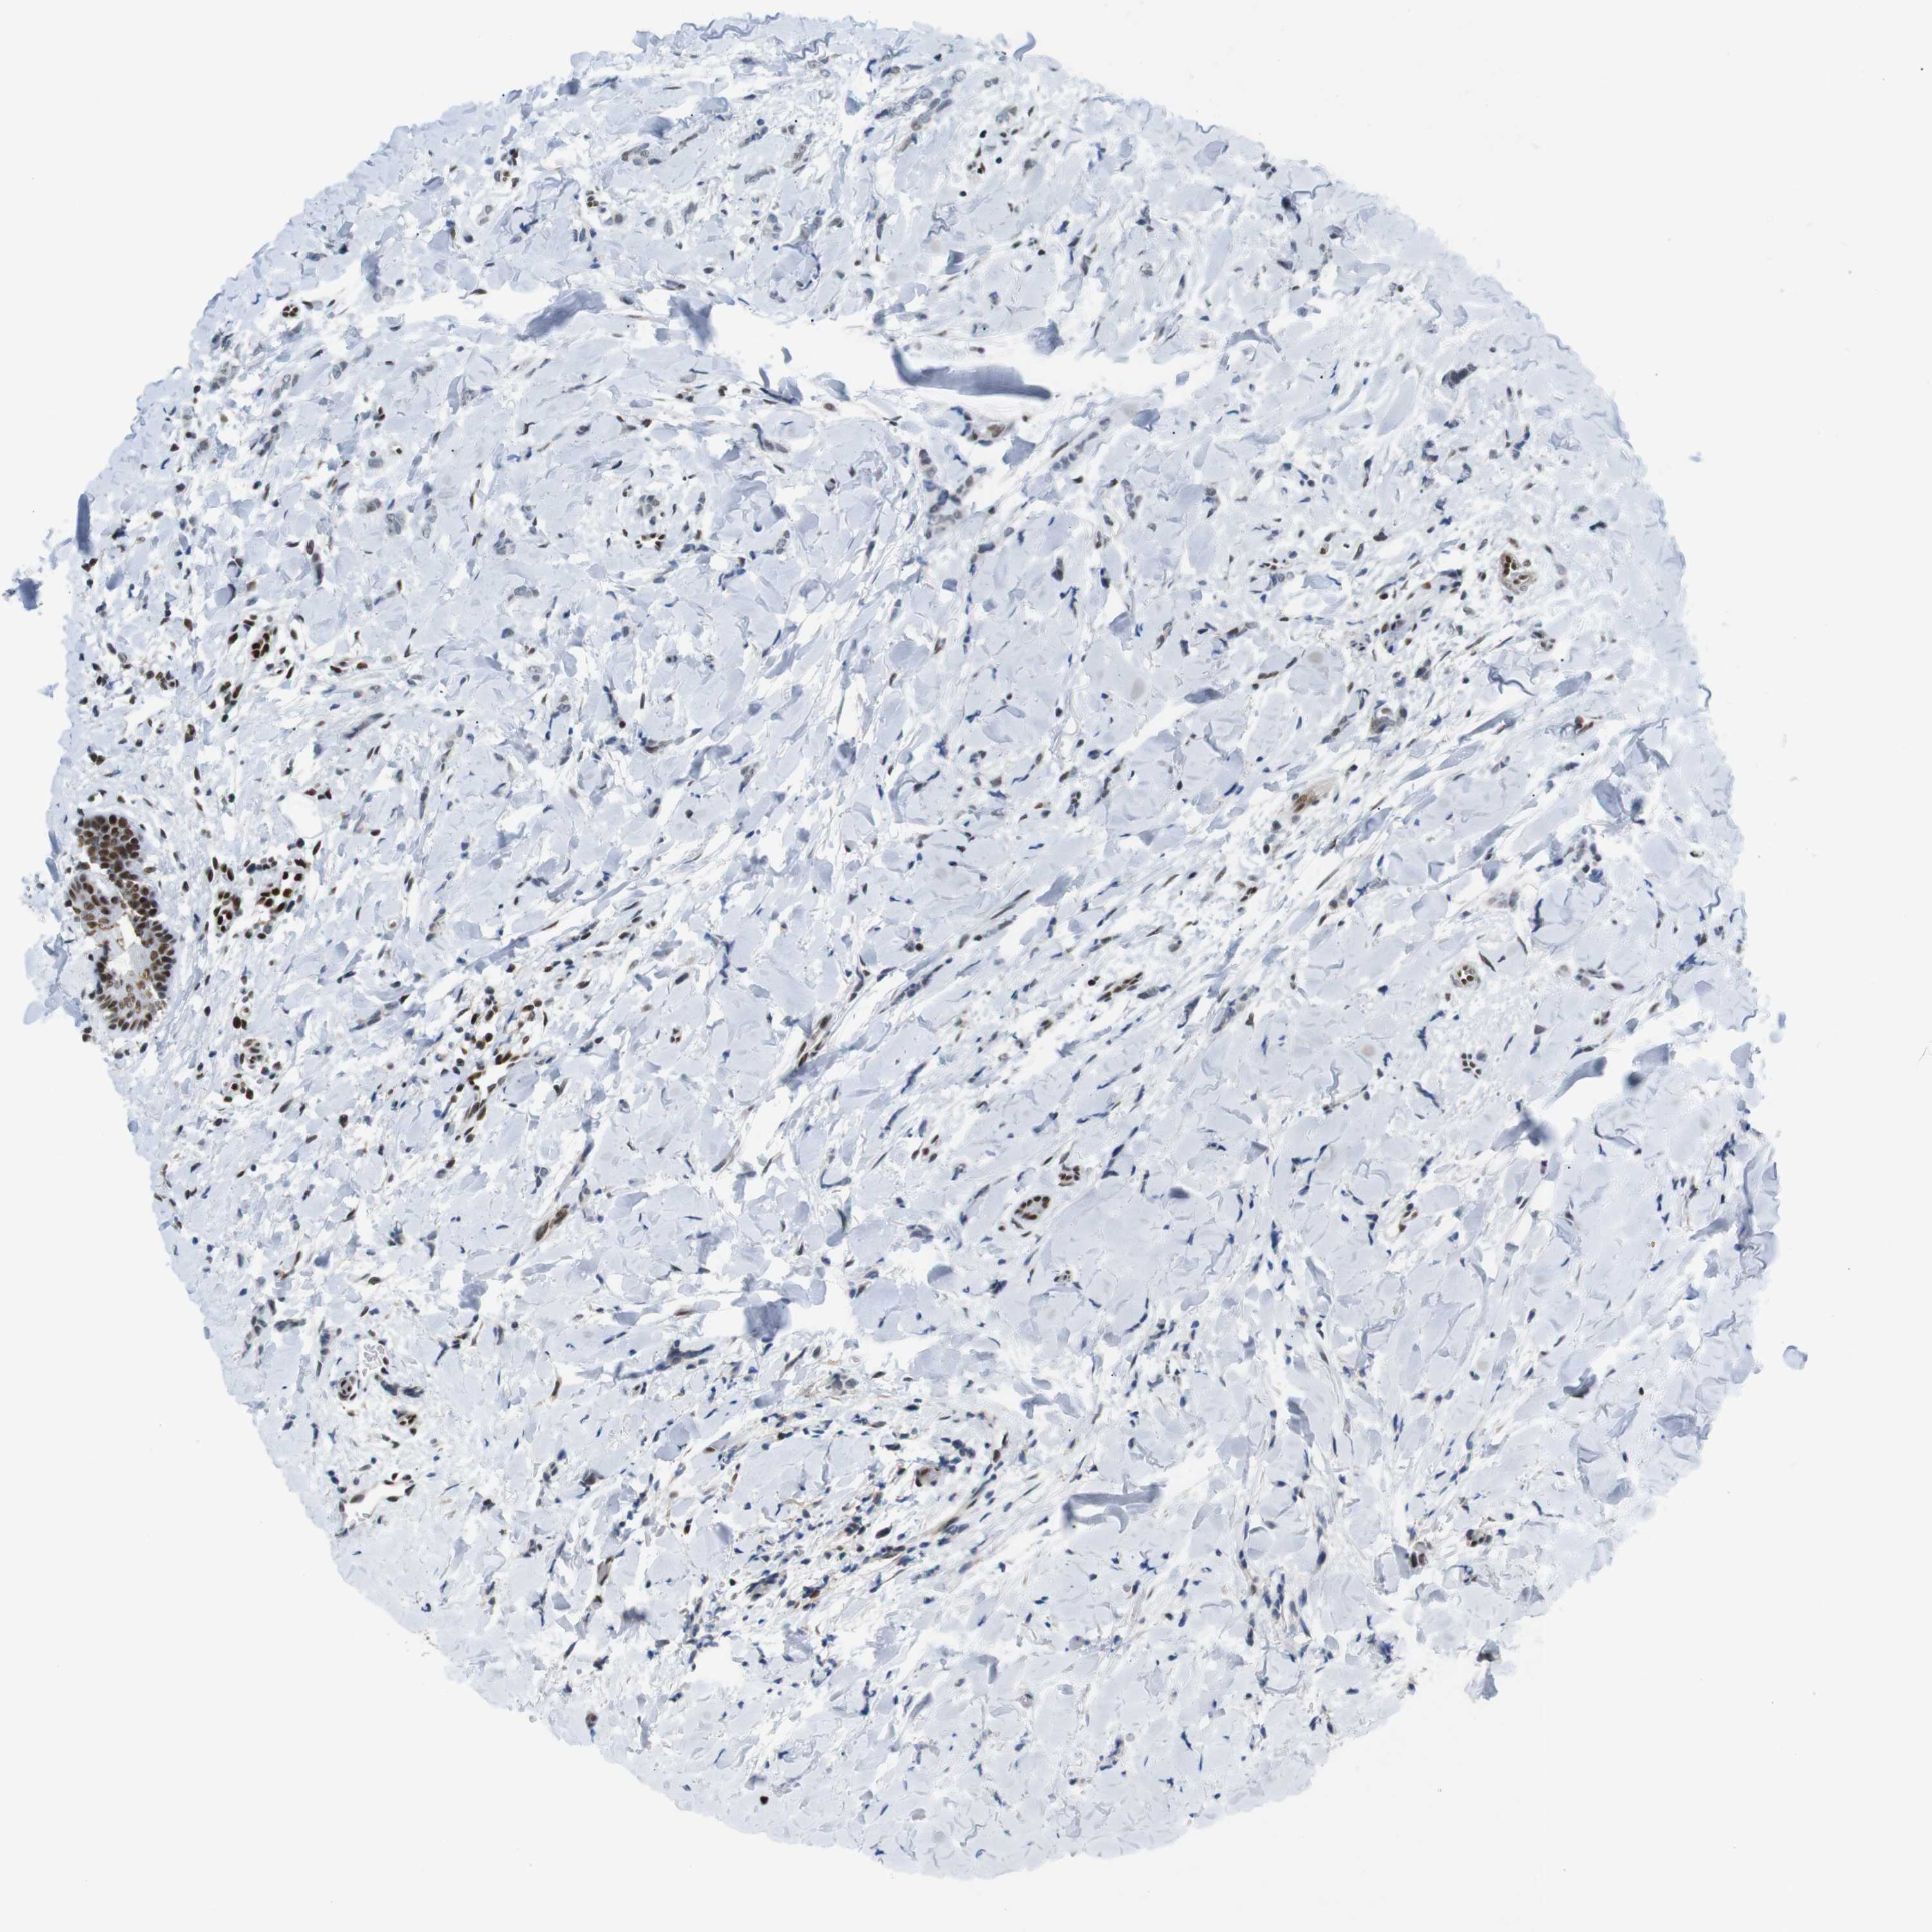

CANCER BREAST CANCER Show tissue menu

BRCA TCGA BRCA VALIDATION PROTEIN EXPRESSION

RIOX2 is potential prognostic, high expression is unfavorable in Breast Invasive Carcinoma (TCGA)